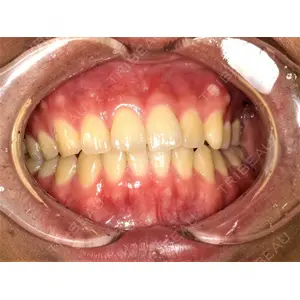

この施術の参考症例

/uploads/case_report_image/file/264500/94db6a07-a97f-4013-a3ca-8748b689b24c.jpg)

/uploads/case_report_image/file/264499/61572a37-d262-4057-b544-5bc59cd841b9.jpg)